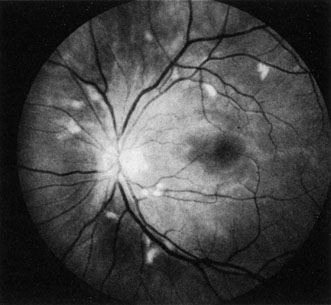

When a branch retinal artery is obstructed, there is usually whitening of the retina in the area supplied by the artery (Fig. 2). In most eyes (62% in one series), emboli are responsible for the obstruction.94 The temporal branch arteries are involved in almost all cases that have been reported,92,94 but whether this is because nasal branch retinal artery obstructions are rare or because such obstructions are simply asymptomatic is unknown. The characteristics of a branch retinal artery obstruction on intravenous fluorescein angiography are similar to those for central retinal artery obstruction.